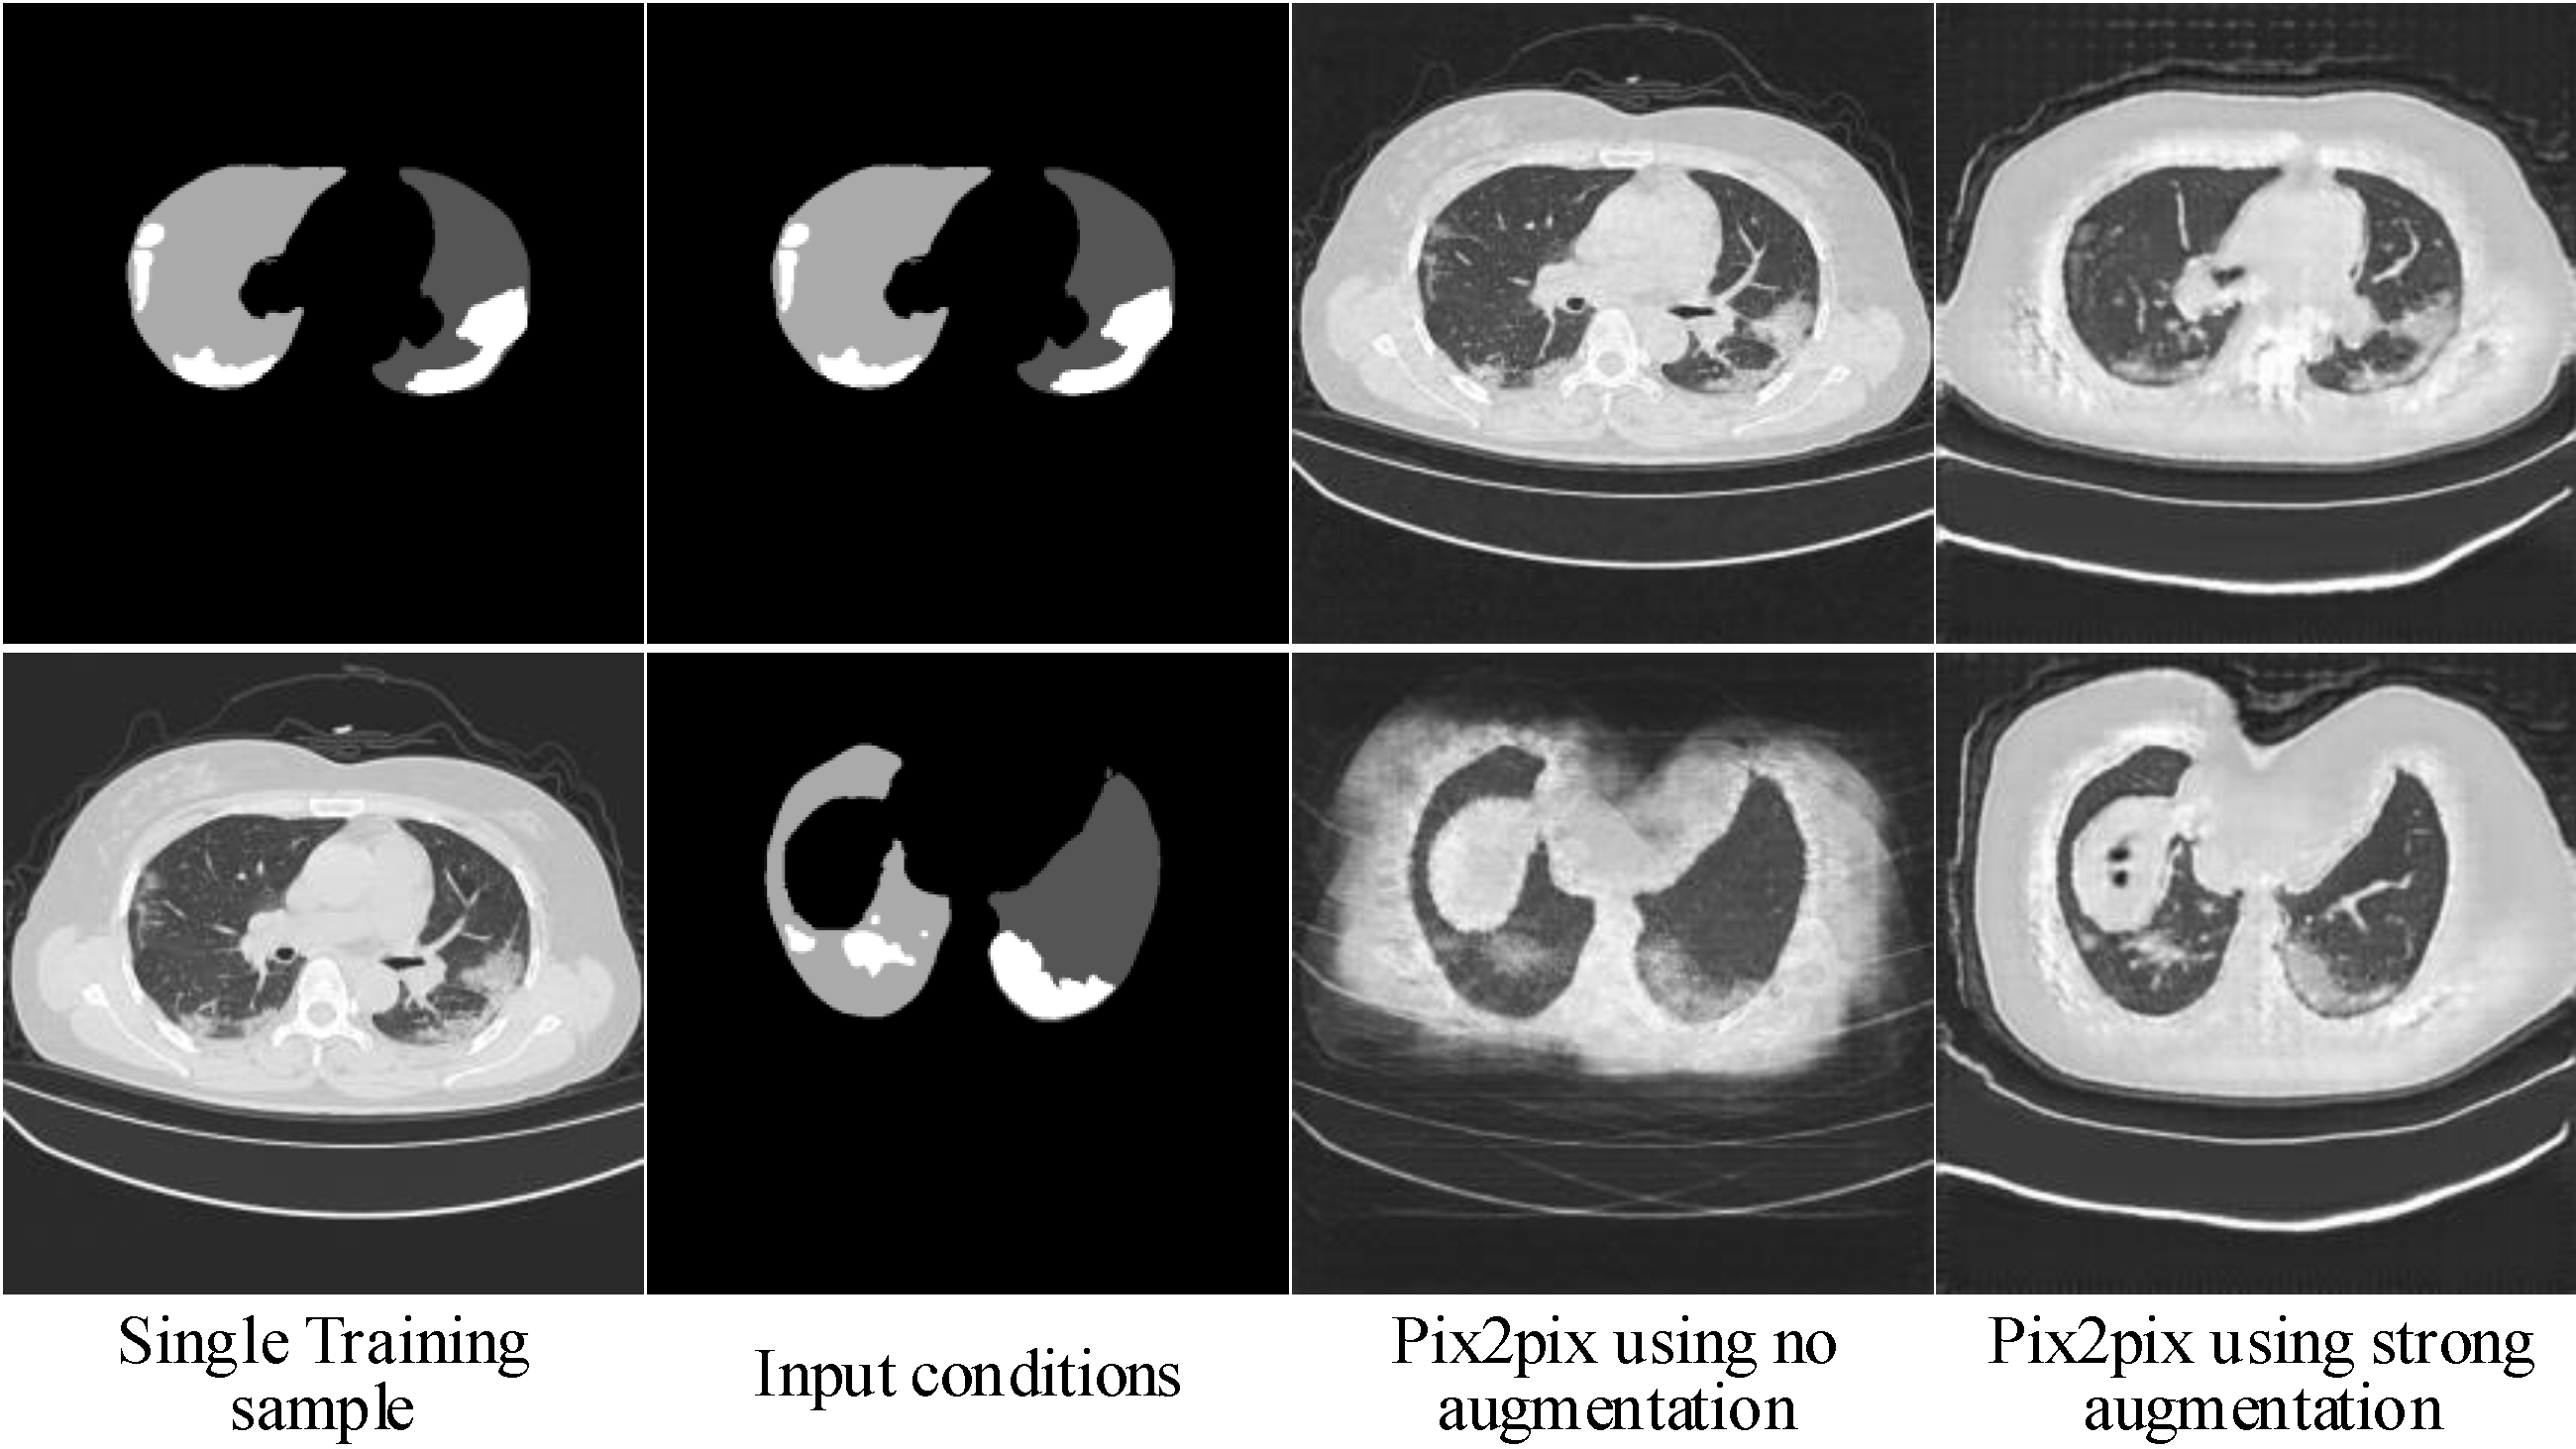

2.1.3. Hierarchical Data Augmentation

- SA is critical for to generalize to different input conditions.

- WA helps to fit the real image distribution without introducing additional learning burden.

- Decreasing the intensity of SA along with the increasing of image scales can handle the balance between fitting conditions and fitting images well.